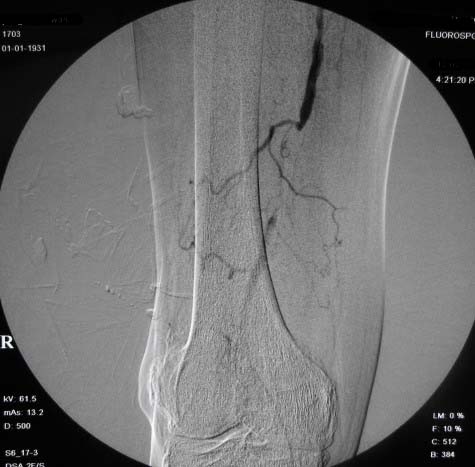

右下肢:

右侧股浅动脉上、中段多处狭窄,下段闭塞。左侧股浅动脉多处狭窄,国动脉起始部狭窄。可以用球囊扩张配合动脉内溶栓或股浅动脉支架置入。多为糖尿病所致。

双侧股动脉及腘动脉多发狭窄,右股动脉下段闭塞并侧支形成。病变较广泛,球囊可试试,如病人经济不好,最好还是以药物治疗为主。个人意见。